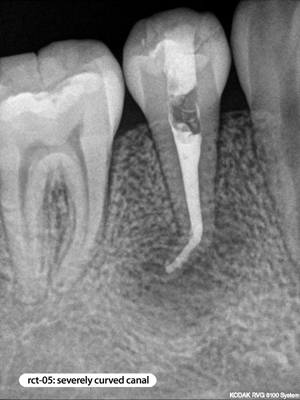

Root Canal Cases